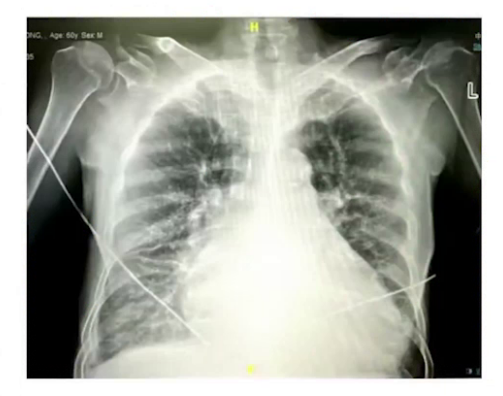

胸片:双肺淤血、纹理模糊、散在斑片影、双侧胸腔积液、双肺肺气肿改变、散在实性小结节、右肺中叶及左肺上叶条索影、双肺下叶多发实变影及间质性改变。